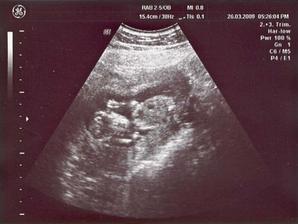

26/3 09 PORADNA 14 + 4 tt - přítel nesmí chybět, žížalka povyrostla, je to mrška neposedná, ani chvíli není v klidu, dr. má problémy vystihnout okamžik aby byla fotka z utz pěkná, nakonec máme fotečky dvě, na jedné jdou vidět oči - vypadá jak marťan 🙂), dr. slíbila že na příští KO už budeme vědět pohlaví ... čekání do 28/4 bude nekonečný